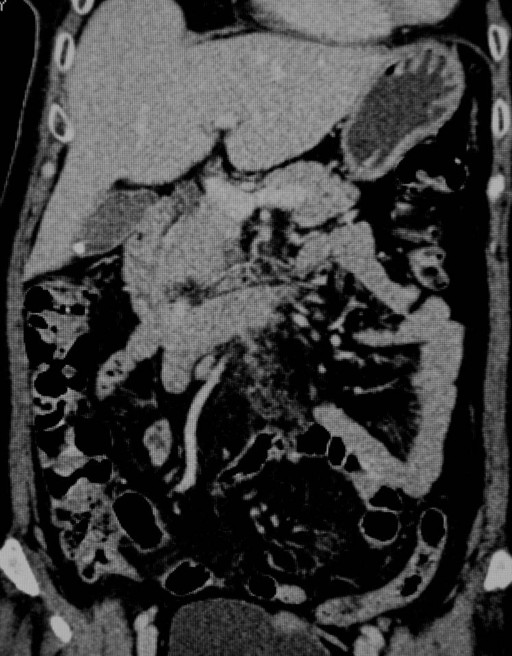

As the patient was mildly symptomatic and stable, she was referred to the gastroenterology service and was admitted to the general medical ward. She was kept nil orally, started on intravenous fluids and omeprazole, and given blood and fresh frozen plasma transfusions to correct the anemia and the coagulopathy. Her condition remained stable and her symptoms improved over the next few days. Her abdominal distension and vomiting regressed and she was allowed oral feeding. Echocardiography showed a normal left atrium without any evidence of clots. She was discharged seven days after admission but was not started on her aspirin and warfarin. Repeat urinalysis before discharge showed resolution of the microscopic hematuria. A repeat CT scan two months later showed that the hematoma and the other abnormalities seen on the initial CT scan had completely regressed (Figure 2). She has begun her anti-coagulants again with close monitoring and has remained well on follow-up without further abdominal pain or hematuria.

Figure 2. Reconstructed CT scan showing complete resolution of the jejunal hematoma and bowel obstruction. A solitary gallstone was also seen in the fundus of the gallbladder. |